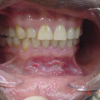

Ülemise hambakaare kitsenemine ehk tagumiste hammaste risthambumus

Hammustades on näha, et alumine hambakaar on laiem kui ülemine. Tagumine risthambumus võib olla kas mõlemapoolne või ühepoolne ja sageli hambakaarte keskjooned hammustades ei ühti. Tagumist risthambumust võib esineda 10...